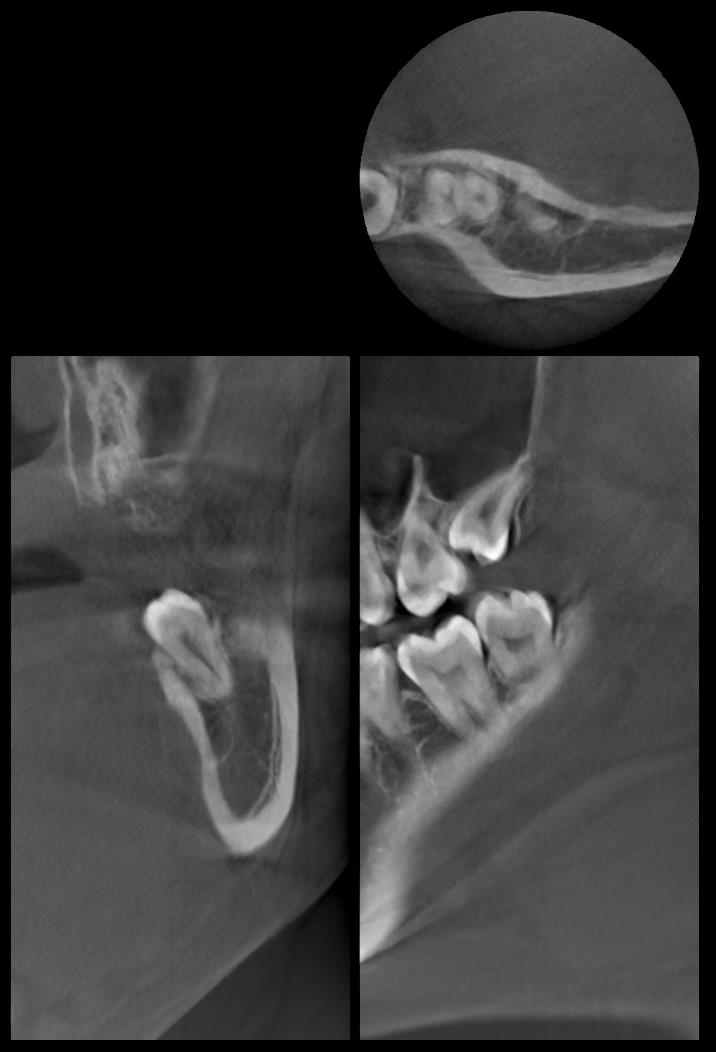

術前CT写真 (左上下)

術前CT写真 (左上と左下)

CT画像で状態を確認し、親知らずの歯根の曲がり具合や歯根の太さ、

下の親知らずの場合は下歯槽管神経との距離、

位置関係や骨の厚みなどを確認します。

下歯槽神経を傷をつけないように注意が必要です。

この場合、神経との距離を測り慎重に抜歯しないといけません。